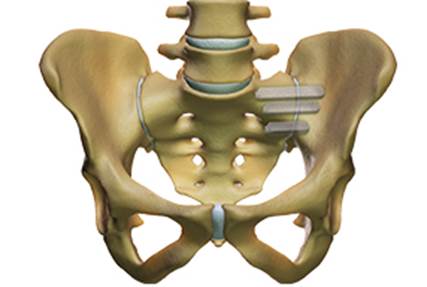

El tractament quirúrgic de l’articulació sacroilíaca dolorosa està indicat únicament en casos d’en què la teràpia conservadora ha fracassat durant un mínim de 6 mesos. Davant d’un dolor persistent i crònic es pot realitzar una cirurgia mínimament invasiva que consisteix en la introducció percutània de tres implantes de titani de perfil triangular mitjançant l’ili i del sacre. D’aquesta manera queda bloquejada l’articulació sacre-ilíaca en tots els seus graus de llibertat.

En els últims anys s’han realitzat més de 30.000 procediments en tot el món. Els estudis clínics demostren una millora significativa en la qualitat de vida del pacient després la cirurgia en comparació amb pacients tractats sense cirurgia.

Caracterització de fusió quirúrgica percutània de l’articulació

sacre-ilíaca esquerra mitjançant 3 implants de titani de perfil triangular..

El Dr. Morgenstern és un cirurgià acreditat per a la realització de la tècnica de fusió percutània de les articulacions sacroilíaques.